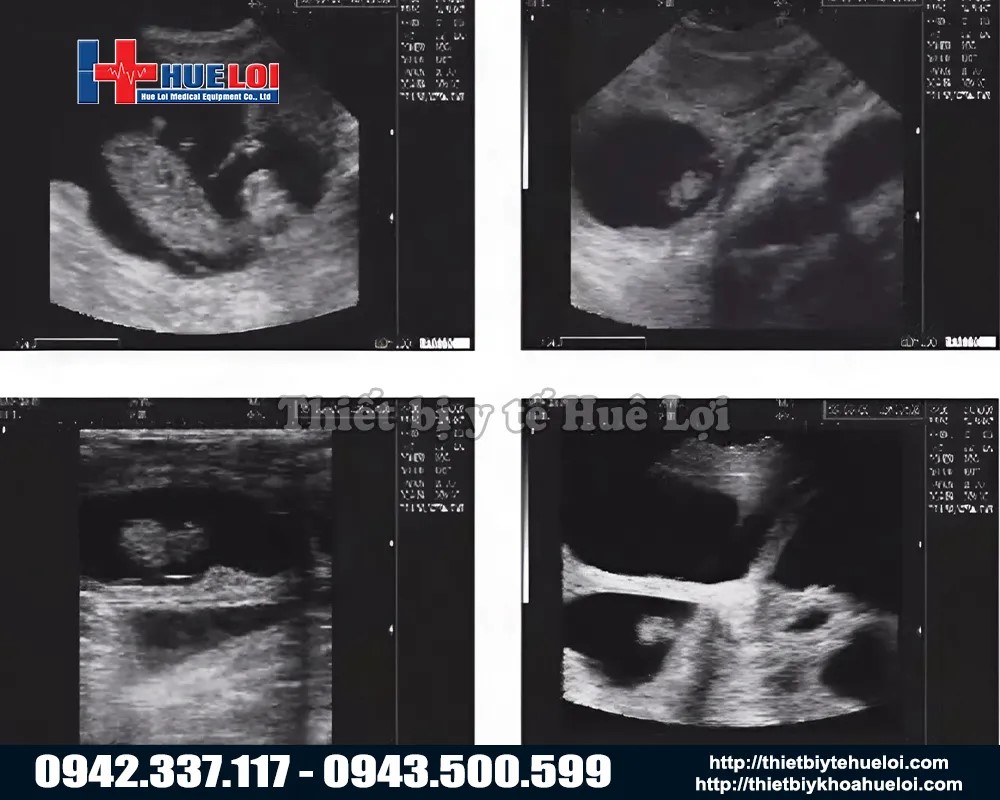

- Công Nghệ Hình Ảnh "Mimage" Vượt Trội

Dù là máy cầm tay nhỏ gọn, M3V được trang bị nền tảng siêu âm y tế với công nghệ hình ảnh "Mimage", mang lại chất lượng hình ảnh chẩn đoán sắc nét và rõ ràng đáng kinh ngạc. Với màn hình LCD 7 inch lớn so với các dòng cầm tay (thường chỉ 5-5.5 inch). Tỷ lệ 16:9 giúp việc quan sát các chi tiết nhỏ trở nên dễ dàng hơn bao giờ hết.